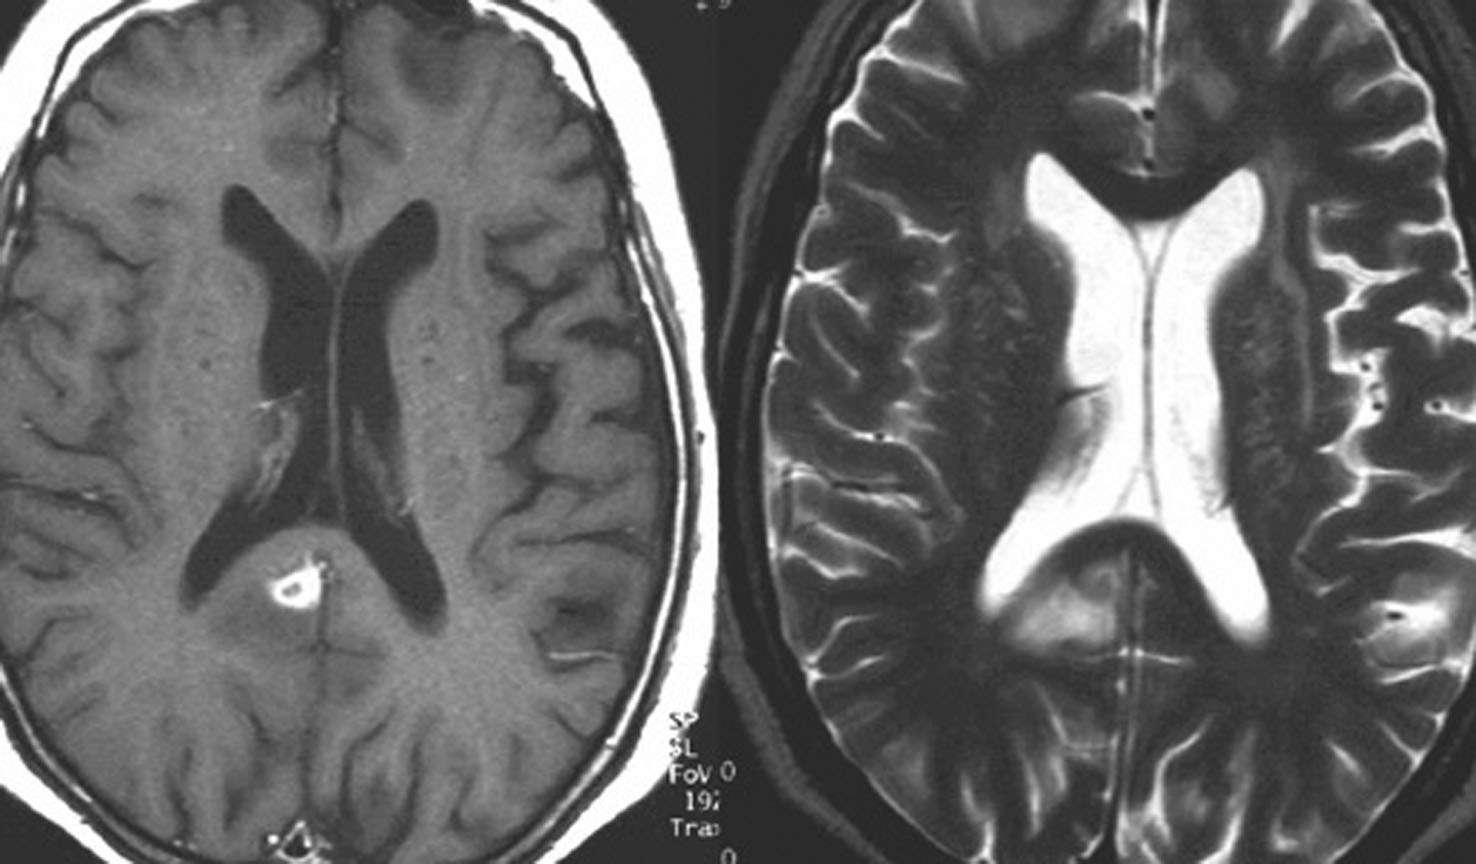

矢印の所を定位脳手術で取りました。病理の結果がリンパ腫と確定されましたから,MTX化学療法をしてから放射線をあてたら,右側のMRIのように腫瘍は消えました。患者さんの症状は良くなって退院したのですがーー。

左から,1回目の再発,2回目の再発,3回目の再発です。再発するたびになんとか治療はできるのですが,違った場所に再発してきてだんだん治療が効かなくなってくることが多いです。このような現象から,脳のリンパ腫は脳に発生するのではなくて,体のどこかに原発巣があるのではないかという考えもあります。もちろん、こんな再発をしないで治ってしまう患者さんも多いです。